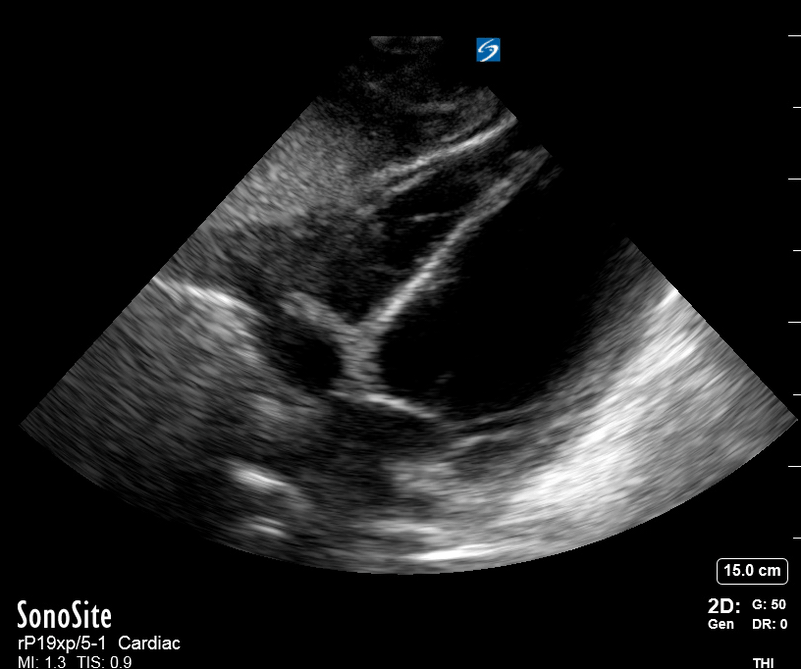

M-mode is used to demonstrate RV collapse (arrow) occurring right after mitral valve opening during diastole. (star = pericardial effusion, 1. RV free wall, 2. Interventricular septum, 3. mitral valve, 4. LV free wall). From: The "5Es" of emergency physician-performed focused cardiac ultrasound (11).